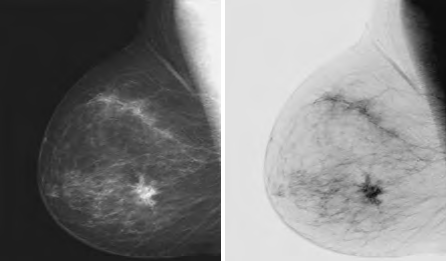

这种变换适用于增强嵌入图像暗区的白色或灰色细节。例如,在数字X线照片中分析身体结构组织。